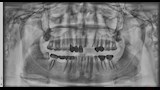

وأشار إسلام إلى أن معاناته بدأت بعد العملية مباشرة، إذ لم تلتئم اللثة رغم مرور ستة أشهر، وبدأ يشعر بإعياء ومشكلات دفعته للتوجه إلى طبيب آخر، والذي طلب منه إجراء أشعة مقطعية وأشعة بانوراما. وقال إنه فوجئ بتشخيص الطبيب بوجود تآكل شديد بعظام الفك العلوي في مواضع الزرع، ووجود خُراجين صديديين، بالإضافة إلى استقرار أحد مسامير الزرعات داخل الجيب الأنفي، وعدم ثبات الزرعات في مكانها.

وأوضح أن عدة أطباء أكدوا له أن هذه المضاعفات نتجت عن العملية، وأن الطبيب الذي أجرى الزراعة لم يطلب أي فحوصات أو إشعات قبلية، مشيرًا إلى أن بعض الأطباء رفضوا كتابة تقارير طبية بالحالة “حتى لا يضعوا أنفسهم في موقف محرج مع الزملاء”.

وأكد إسلام أن الطبيب ع.ع أنكر النتائج التي أظهرتها الأشعة، زاعمًا أن مشكلته تقتصر على ضرورة إزالة مسمار واحد فقط، بينما تنصّل الطبيب الآخر أ.ع صاحب المركز الذي أُجريت به العملية، من المسؤولية وطالبه بالرجوع للطبيب الأول.